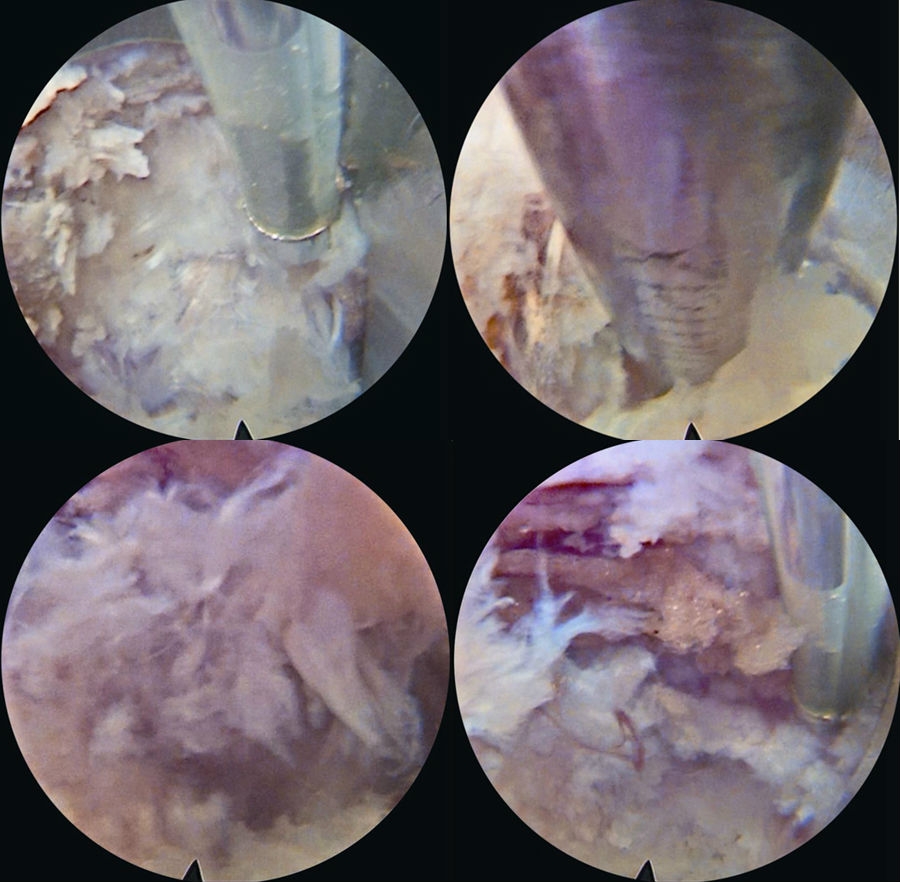

8. 镜下操作

采用一次性双极射频手术刀头、Punch钳、小直钳、磨钻依次切除或修整部分肥厚或钙化的黄韧带、椎体后缘增生的骨赘、椎体后缘对神经根造成压迫的外层纤维环及其边缘的硬化或骨化结构、与后纵韧带粘连的增生结缔组织,对神经根背侧和腹侧进行全面的减压松解,特别是神经根下方的微小硬化性组织。(图16~图21)

图17-图20 内镜下显示套管内视野中间纤维环;内镜下小直钳取髓核;取出部分髓核后张力下降,神经张力间接下降;转动工作套管显露硬膜囊和周围组织

9. 双极射频使破裂的纤维环消融皱缩成形。观察可见硬膜囊自主搏动,神经根表面血运明显改善,血管充盈,神经根复位,术中行直腿抬高试验,可见神经根被牵拉后滑移自如。(图22、图23)

10. 旋转工作套筒检查视野内无出血、残余碎片等,确认无异常后移除内镜及工作套管。切口缝合1~2针。(图24)

图21-图24 取出的髓核组织(中间部分硬化);下行根头端减压;硬膜囊、下行根减压后神经松解,博动良好;手术切口(大小约8mm)

5. 黄韧带扩孔,直视镜下沿黄韧带裂隙将锥形工作套管轻柔地旋转入椎管,可见破碎的髓核组织及纤维环组织。(图30~图35)

6. 确定髓核组织后,用镜下髓核钳将突出髓核组织切除(图36~图40),直至清晰地看到后纵韧带和神经根周围脂肪组织。

7. 双极射频刀头电极在直视下行残存髓核组织消融止血,纤维环破口皱缩成形。(图41)

8. 减压充分的标志是可在镜下看到神经根及硬膜囊随呼吸波动(图42),仔细探查无脱出髓核残留后,退出内镜系统,伤口缝合

图31-图34 篮钳咬除硬膜表面黄韧带;篮钳咬除黄韧带并注意隆起的硬膜囊;

剥离子插入突出髓核并开始旋转工作套管;

继续旋转工作套管,借助套管头端将神经从髓核表面移开

图35-图38 下行根和硬膜囊已经从髓核表面移开;髓核摘除,白色为突出髓核;

髓核摘除过程中;髓核被拖出过程中

图39-图40 大块髓核被拖出;大块髓核被清除过程中

图41-图42 双极射频止血,纤维环成形;髓核摘除后硬膜囊和下行根减压松解